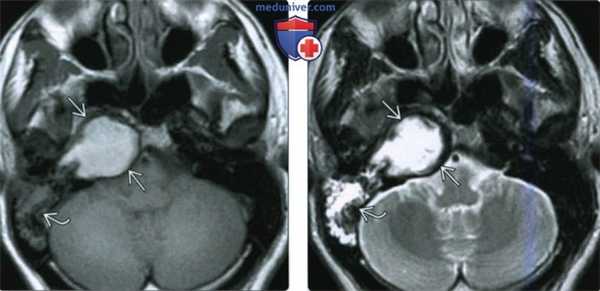

(Слева) При КТ в костном окне определяется распространенное образование с тотальной деструкцией передненаружного края. Образование распространяется в ВСК и приводит к эрозии слуховой капсулы. Кавернозный сегмент ВСА смещен кпереди.

(Справа) При аксиальной КТ височных костей (более каудальный срез) у этого же пациента визуализируется ХГ-ВП, сдавливающая костную часть евстахиевой трубы. Жидкость в сосцевидном отростке обусловлена обструкцией евстахиевой трубы.

(Слева) При аксиальной МРТ Т1 ВИ у этого же пациента визуализируется экспансивная гиперинтенсивная ХГ-ВП. Жидкость в сосцевидном отростке имеет промежуточный сигнал, преимущественно за счет содержания белка.

(Справа) При аксиальной МРТ Т2 ВИ у этого же пациента визуализируется гиперинтенсивное экспансивное образование ВП, в котором находятся мелкие гипоинтенсивные очаги (отложения гемосидерина). Классическая холестериновая гранулема имеет гиперинтенсивный сигнал на Т1 и Т2. «Запертая» жидкость в сосцевидном отростке также гиперинтенсивна.